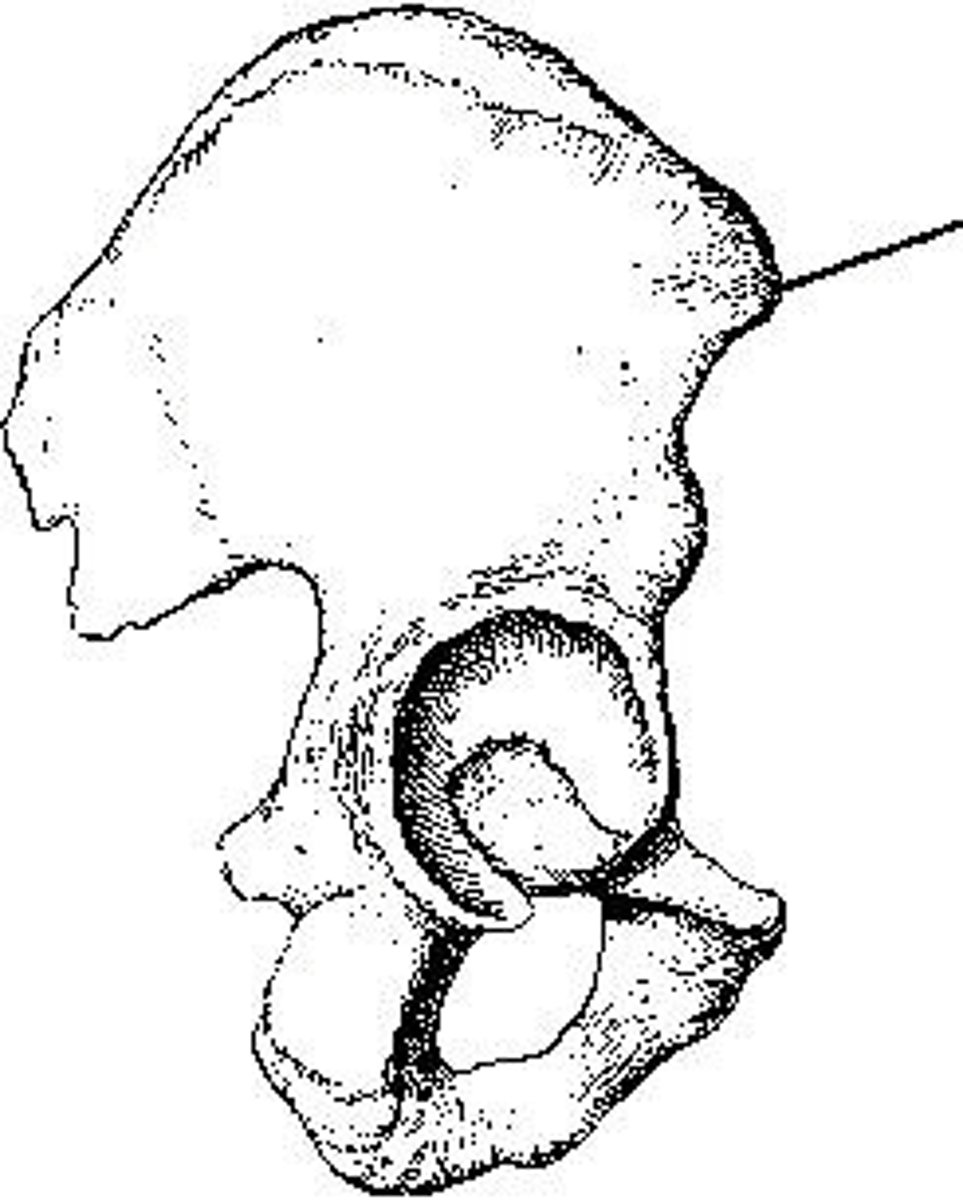

The part identified on the ilium above is the _____ iliac spine.

anterior superior

What anatomy is labeled as letter C in the image below?

ASIS

What anatomy is labeled as letter B in the image below?

Lesser trochanter

The area identified on the bone shown above is the:

intertrochanteric crest

The area of anatomy indicated on the figure above is the:

obturator foramen

What anatomy is labeled as letter A in the image below?

Acetabulum